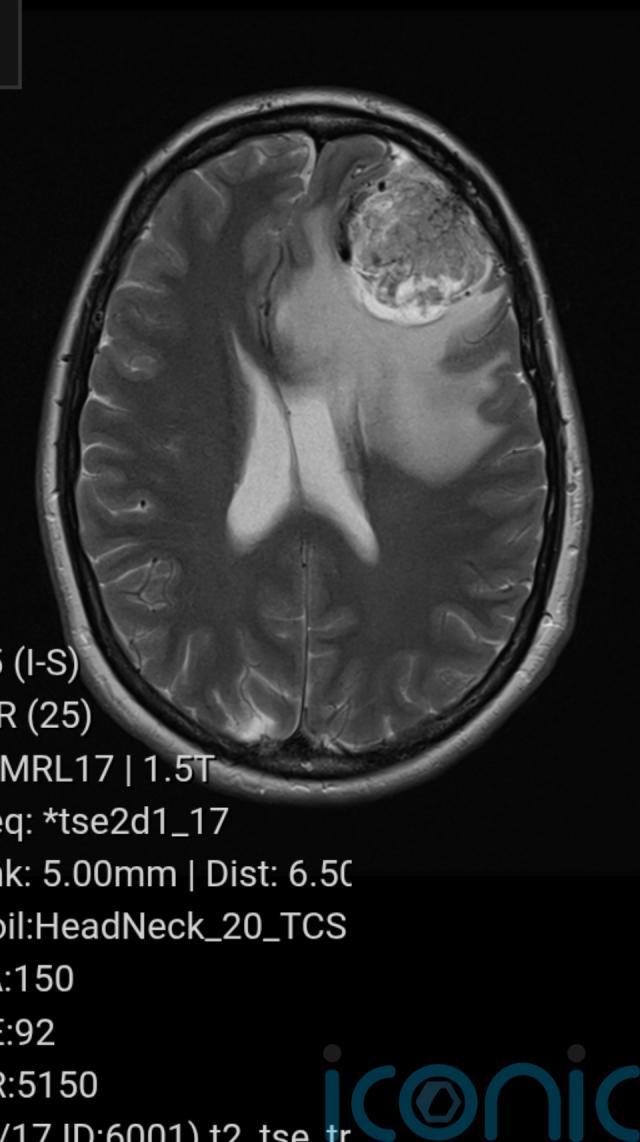

The results of her scan were sent to Medway Hospital, where a doctor informed her there was a “large mass” on her frontal lobe, which was later diagnosed as a meningioma – a non-cancerous brain tumour.

“I was shocked at how big (the tumour) was, and all the extra white stuff around it on the scan was swelling, which was causing all my head pressure.”

The tumour was diagnosed as a meningioma, and doctors suspected “it could have been growing for 20 years”.